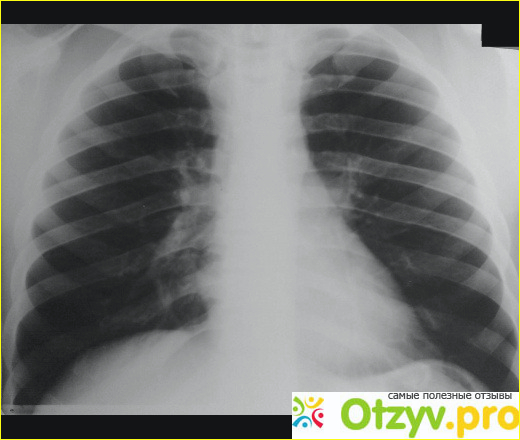

На улице был очень мороз к тому же, мы приехали вечером. В кабинете меня уже ждал врач-пульмонолог, он также меня осмотрел, зарегистрировал мою анкету и сразу же направил меня проходить рентген, на котором выяснилось, что у меня спонтанный гидропневматоракс, как только я узнал, мне сразу же стало плохо, потому что меня также будет ожидать пункция легкого и длительное нахождение в палате, а мне срочно нужно было возвращаться на родину, к тому же я просрочил свои документы, поэтому потом были свои проблемы.

Хочу конечно же похвалить своего лечащего врача, который стал мне вторым отцом в данной больнице. Так вот лечащий врач мало того, что он мне отлично провел операцию, также он мне сказал, что надо завязывать с алкоголем и особенно с сигаретами, я в конечном итоге прислушался к его словам и теперь веду здоровый образ жизни. Также он меня навещал пару раз в день, помогал делать медсестре уколы, приносил обед в комнату, так как передвигаться мне было очень сложно, да к тому же мне опять привязали банку, в которую стекается жидкость с легких. Спонтанный гидропневматоракс связан с наличием в плевральной полости легкого достаточного количества жидкости и воздуха, и их надо было в срочном порядке выкачивать из меня.

Самое главное, что он со мной постоянно поддерживал связь. О результатах анализов врач меня также постоянно оповещал. За эту неделю мне пришлось три раза делать рентген, пару раз я сдавал анализы на мочу, мокроту и на сахар.